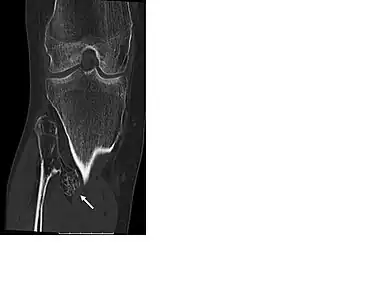

- CT of osteochondroma in MO